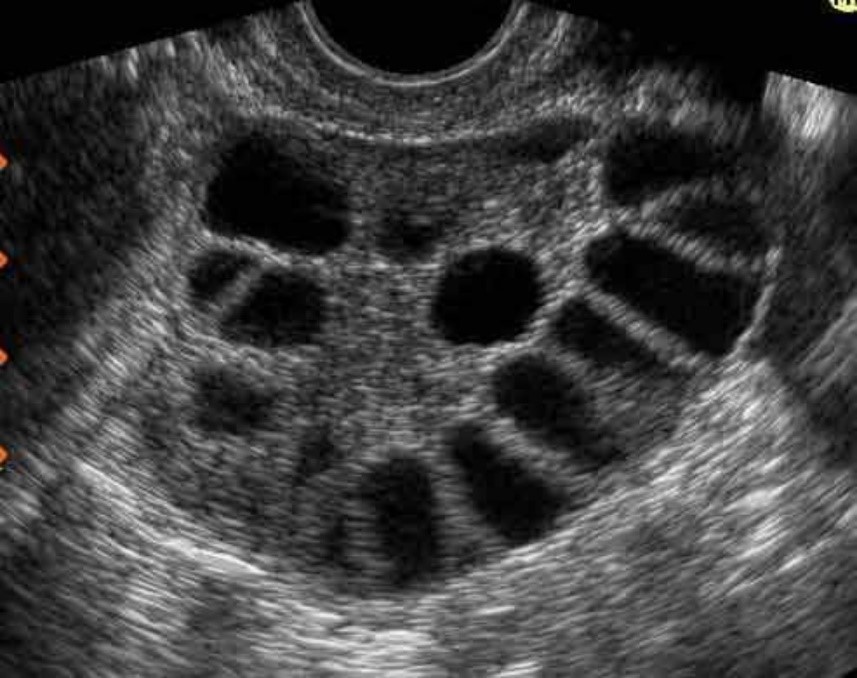

Hội chứng buồng trứng đa nang (PCOS)

Đây là một trong những nguyên nhân bệnh lý phổ biến gây rối loạn kinh nguyệt.

PCOS làm rối loạn quá trình rụng trứng, dẫn đến:

- Kinh nguyệt không đều

- Khó mang thai

- Mụn, rậm lông, tăng cân

Nếu không điều trị sớm, PCOS có thể ảnh hưởng lâu dài đến khả năng sinh sản.